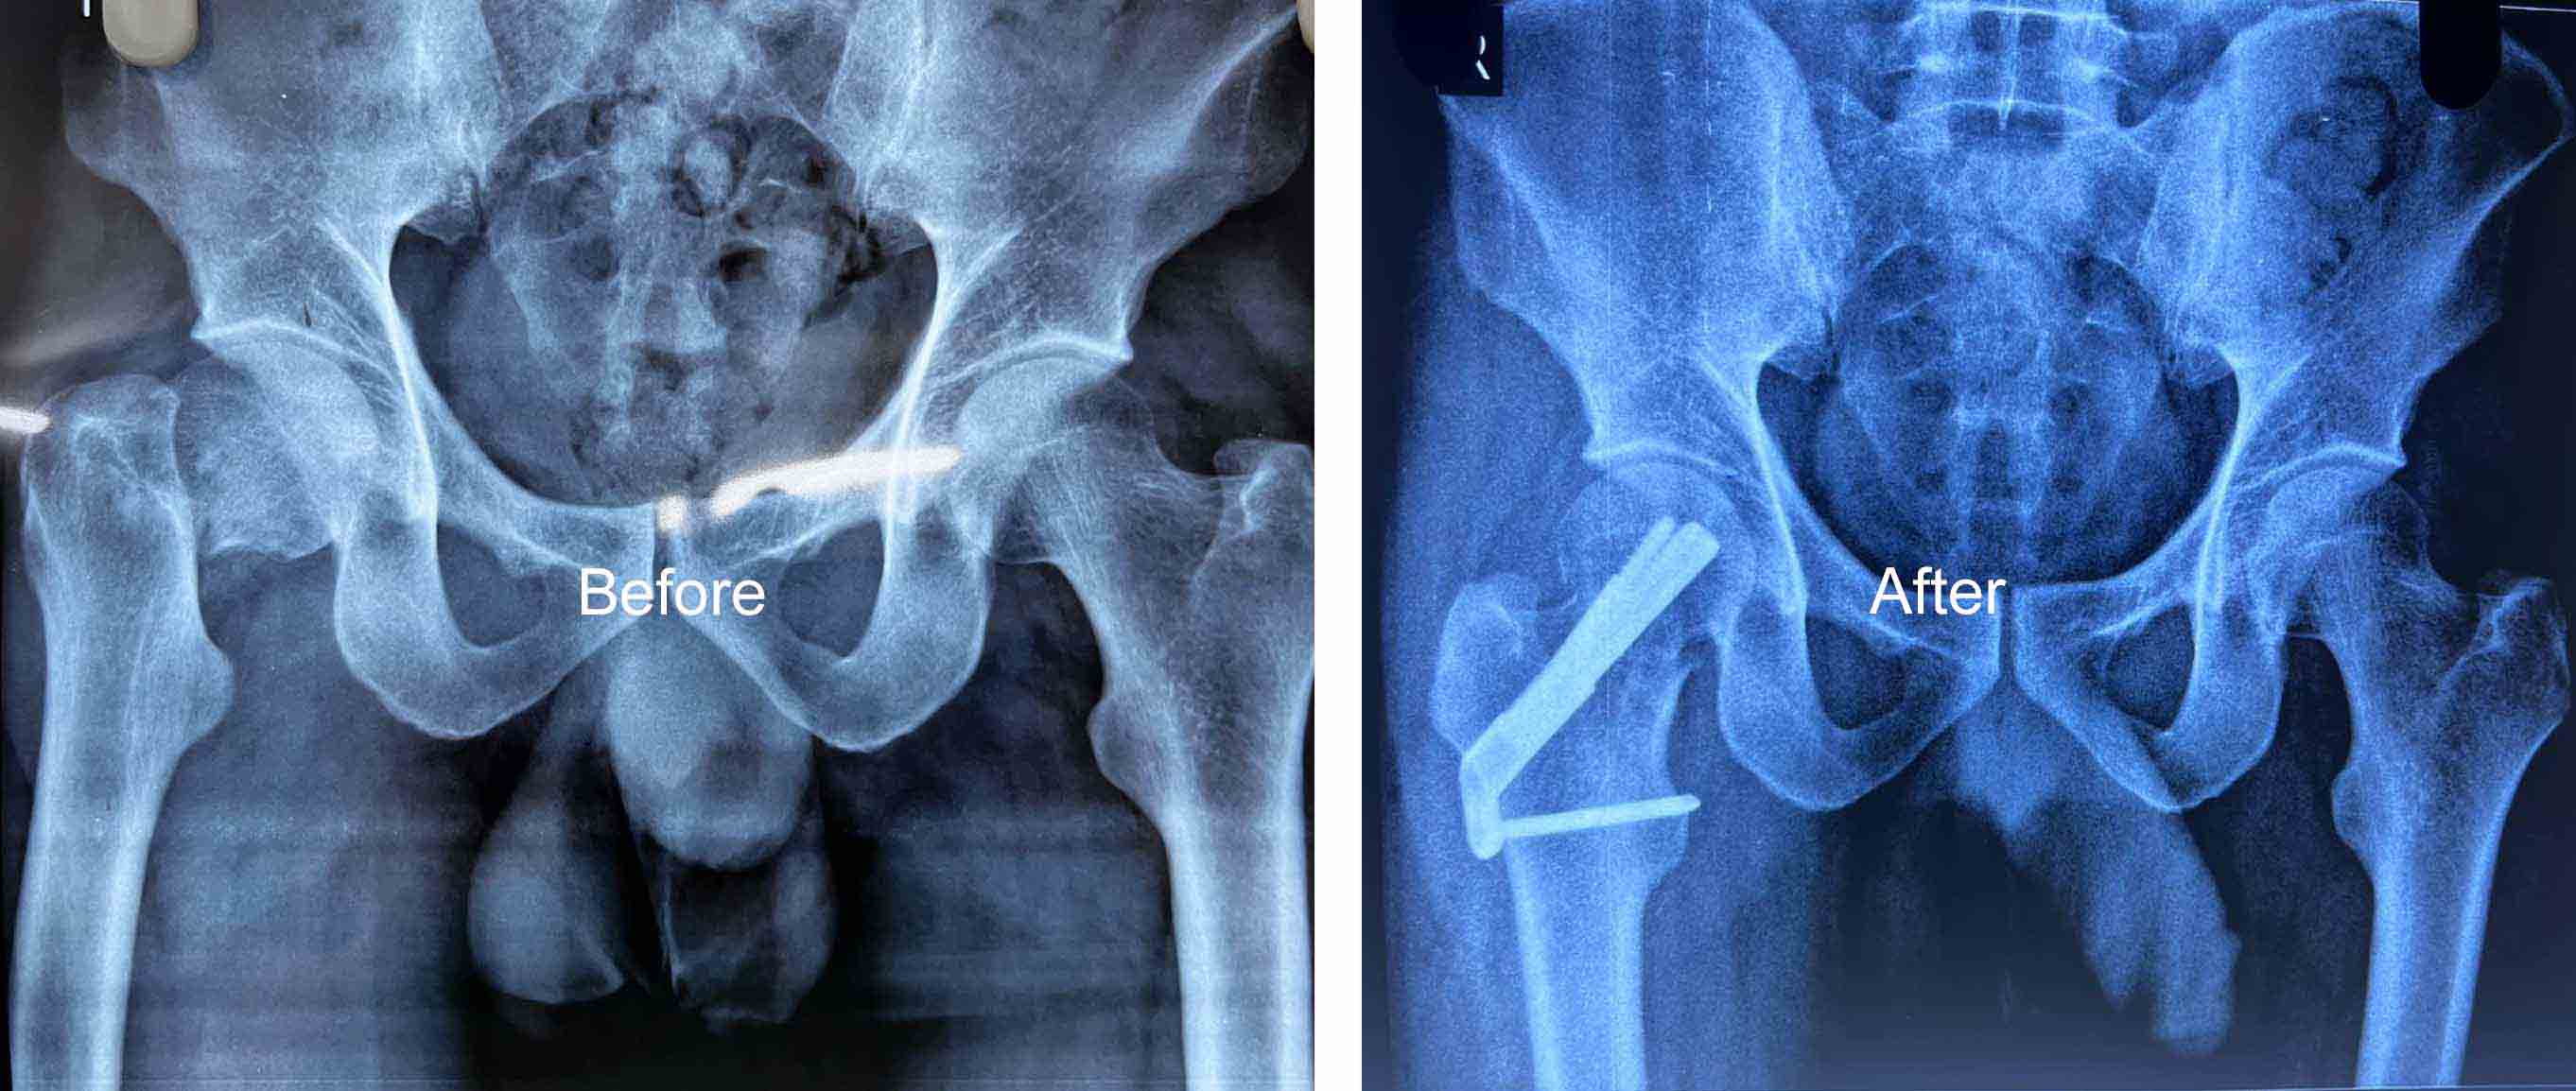

Medical Gallery

Orthopedic Care